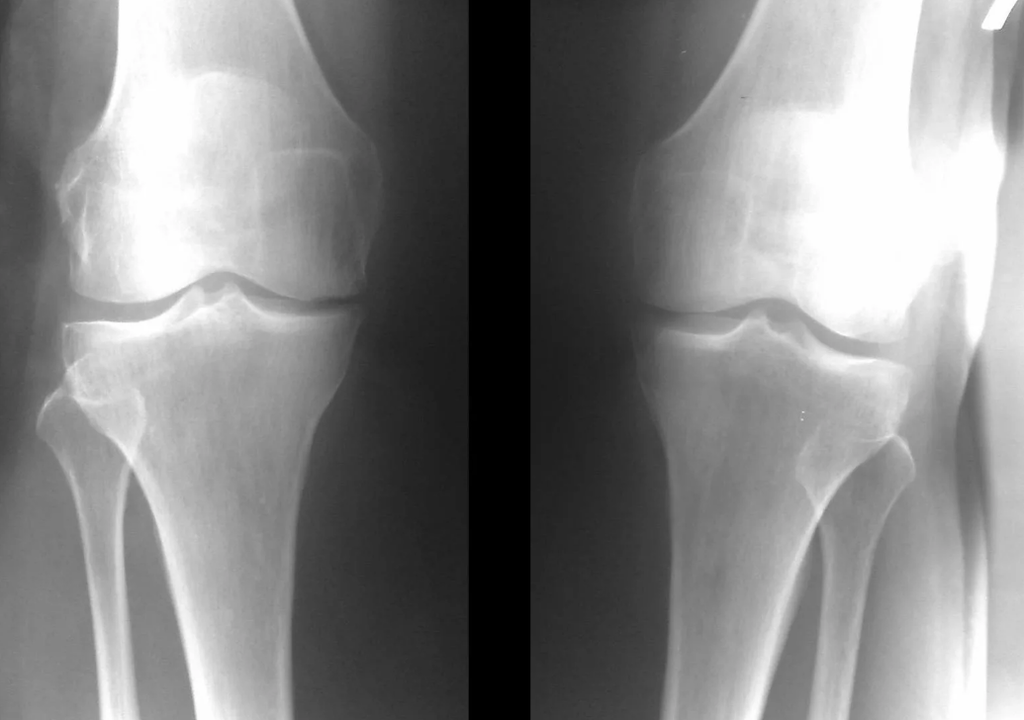

Instrumental diagnosis of arthrosis of the knee joint

In the vast majority of cases, an examination and x-ray of the knee joint in two projections (direct and lateral) are sufficient.Clinical data and imaging help determine the stage of the disease.

In the early stages of the disease, with small changes in bone tissue, radiographic examination is not as valuable.At this stage, gonarthrosis can be diagnosed through arthroscopy.The accuracy of the method is very high;only its invasive nature and price can stop it.

Ultrasonography does not allow clear visualization of changes in the articular cartilage and intra-articular structures.Using MRI, you can detect changes in the bony, cartilaginous and soft tissue structures of the joint, as well as the subchondral bone, with 85% accuracy.Scintigraphy can be used to evaluate the metabolic activity of periarticular bone tissue.